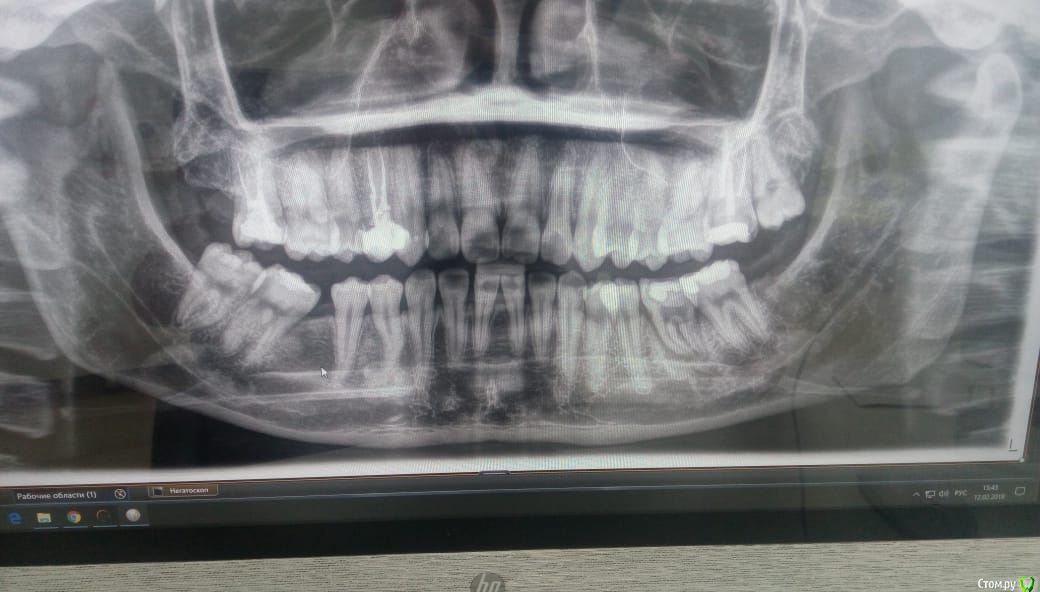

Daniyar Опубликовано 12 февраля, 2019 Поделиться Опубликовано 12 февраля, 2019 FYI 4 Ссылка на комментарий

Jurai Опубликовано 12 февраля, 2019 Поделиться Опубликовано 12 февраля, 2019 сколько времени прошло после вмешательства - на финальном снимке? Ссылка на комментарий

Daniyar Опубликовано 12 февраля, 2019 Поделиться Опубликовано 12 февраля, 2019 сколько времени прошло после вмешательства - на финальном снимке?09/02/19 Ссылка на комментарий